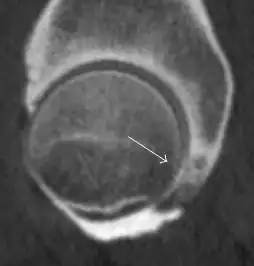

Synovial chondromatosis can be confidently diagnosed by X-ray when calcified cartilaginous chondromas are seen. However, other synovial proliferative processes, such as pigmented villonodular synovitis, require MRI for accurate diagnosis, although noncalcified synovitis can be suspected in radiographs by indirect signs, such as soft tissue swelling and/or erosions in the femoral head, femoral neck, or acetabulum (Figure 7).[1]

Figure 7:

-

Axial CT image of pigmented villonodular synovitis eroding the posterior cortex of the femoral neck.[1]

Sagittal T2* gradient echo image showing a posterior soft tissue mass with hypointense areas secondary to hemosiderin deposition.[1]

X-ray of synovial chondromatosis.[1]

CT of synovial chondromatosis.[1]

In synovial proliferative disorders, MRI demonstrates synovial hypertrophy. In the case of PVNS, characteristic foci of low signal intensity related to hemosiderin deposition are better seen on gradient echo T2* images (Figure 7). In the case of synovial osteochondromatosis, the synovial hypertrophy is accompanied by intermediate signal cartilaginous loose bodies and/or low signal calcified loose bodies.[1]